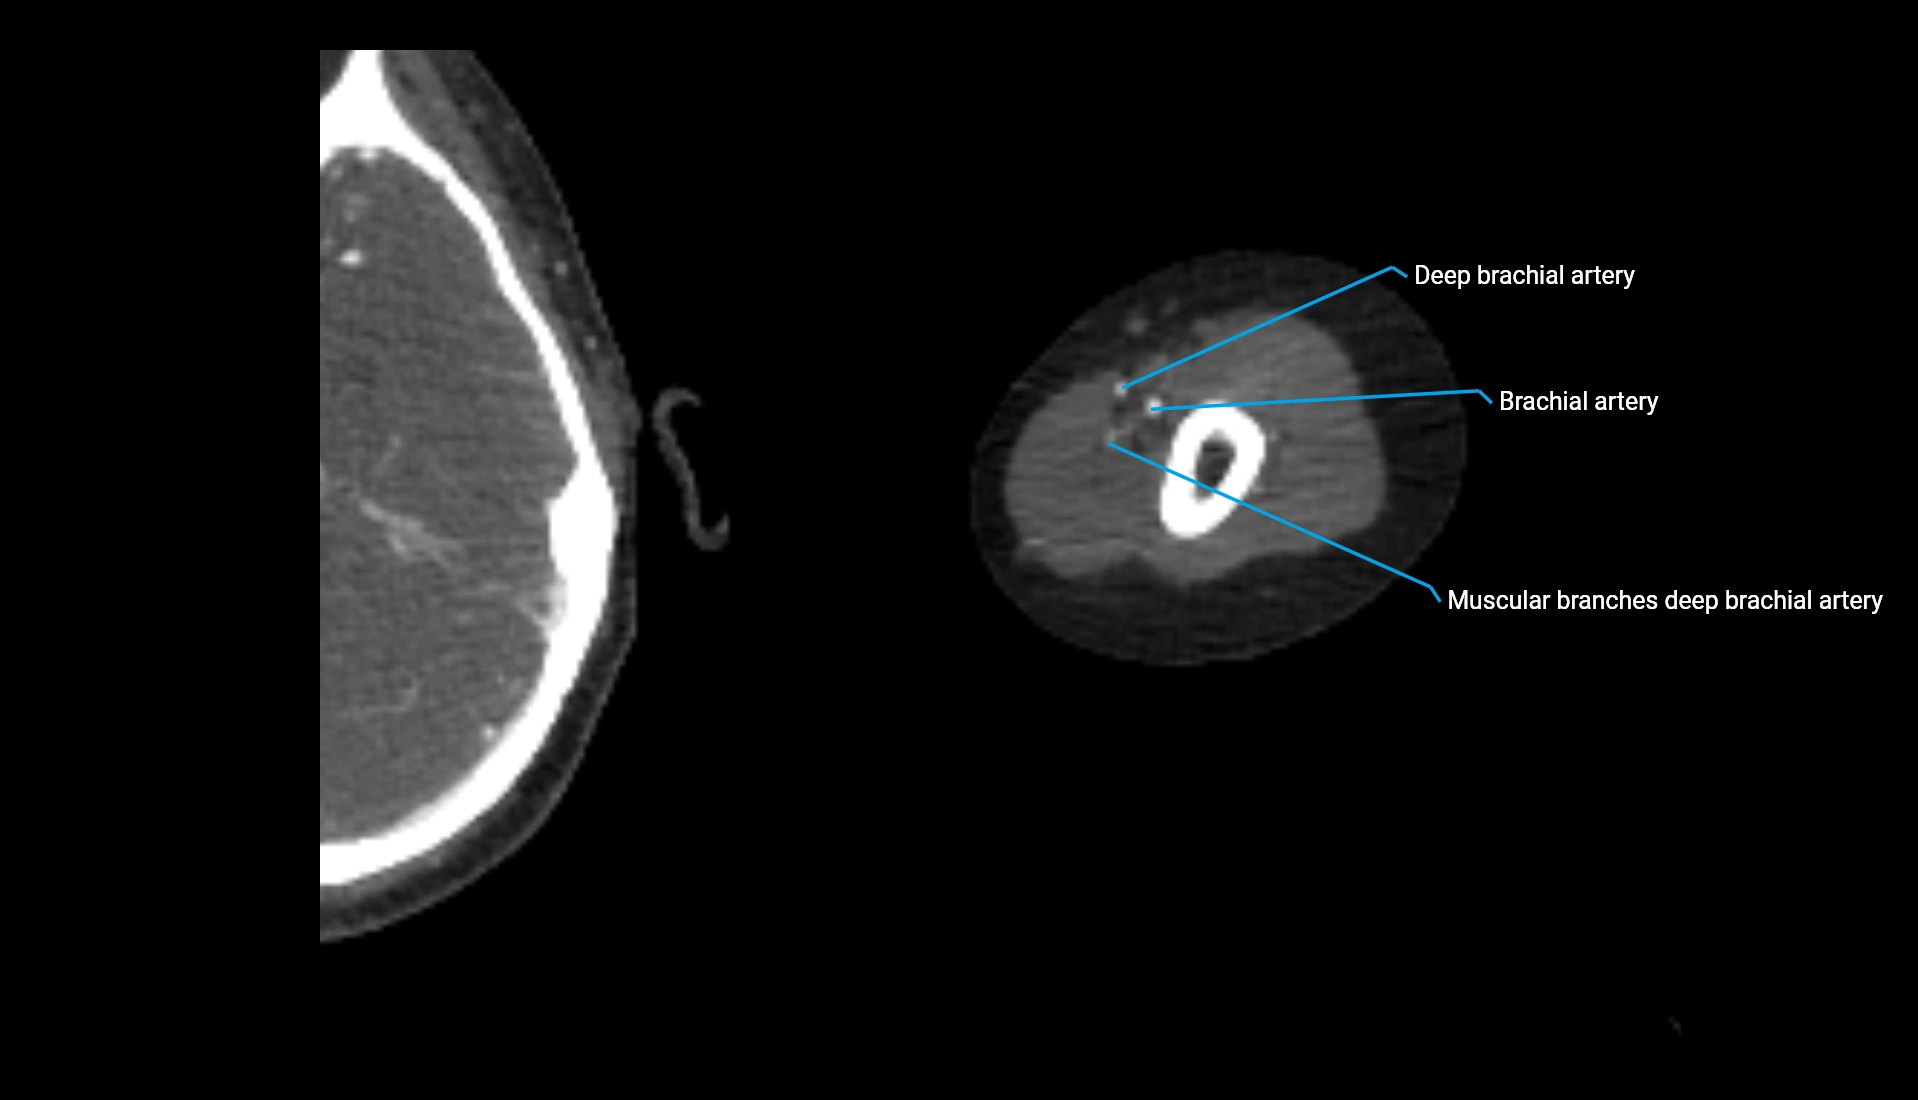

CT Appearance

Non-Contrast CT:

• Cortex: High-density, sharply defined

• Subchondral bone: Dense cancellous matrix

• Articular surface: Smooth concave contour articulating with the capitellum

• Excellent for evaluating bone integrity, alignment, and subtle fractures